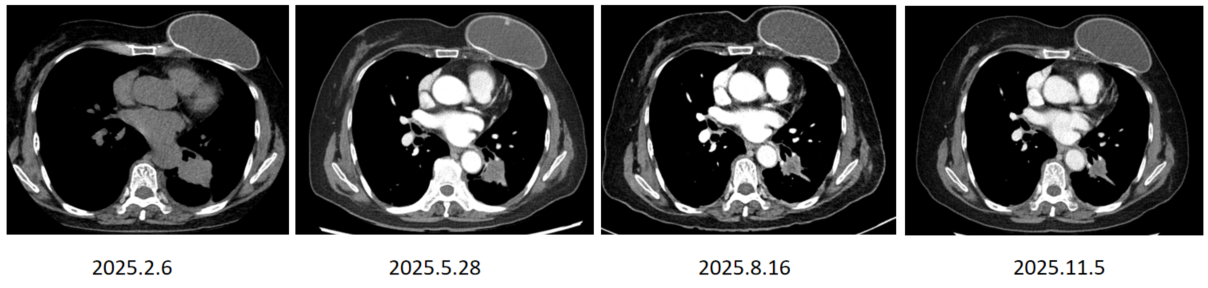

胸部CT( 2024年12月26日):左下叶肿块,多学科会诊(MDT)初步评估倾向于早期肺癌,但患者的手术被推迟了六个多星期。

手术治疗( 2025年2月7日):患者接受电视辅助胸腔镜(VATS)探查术。术中意外发现胸膜种植,遂终止根治性手术并关闭胸腔。

一线治疗: 2025年2月19日-6月12日,患者开始接受兰泽替尼 240mg + 埃万妥单抗(静脉输注,IV)治疗。 2025年7月2日至今,治疗方案调整为兰泽替尼 240mg + 埃万妥单抗(皮下注射,SC)。

疗效评价:胸部CT显示治疗4个月后肺部病灶有所缩小,达到疾病稳定(SD)状态。在将埃万妥单抗IV转换为SC后,左肺下叶的肿瘤病灶持续缩小,截至目前SD超过9个月。